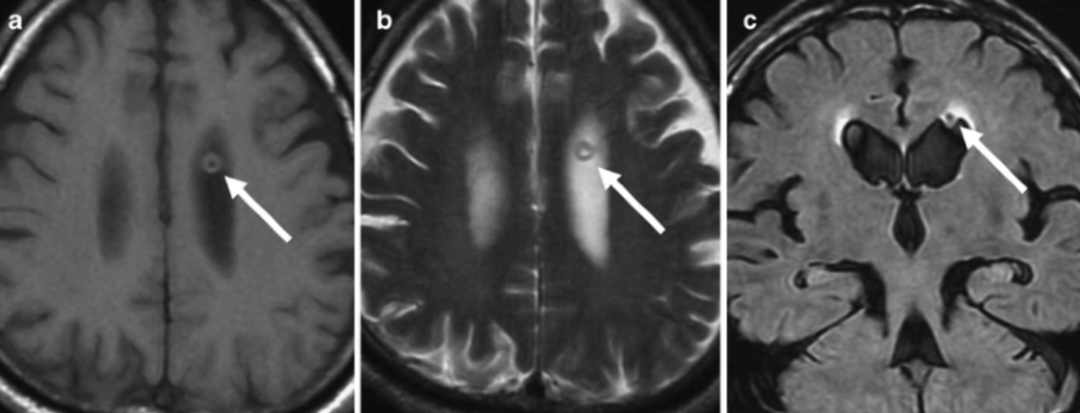

1 例单发的侧脑室环状结节